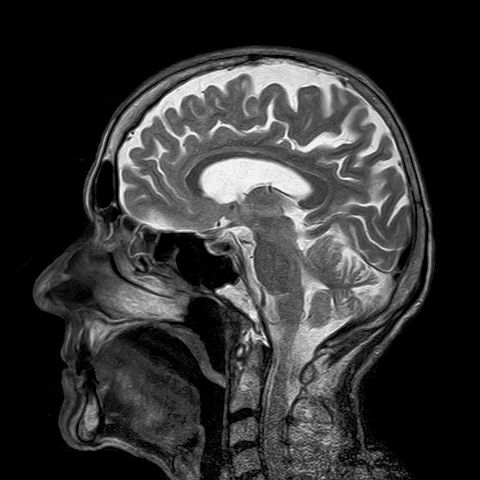

#4 CT scan technologist

You surely cannot expect doctors perform all examinations in ordination. Some technicians control this process, prepare patients, and organize diagnostics procedures. This job is in high demand, for 22% and the average salary is 60,070.